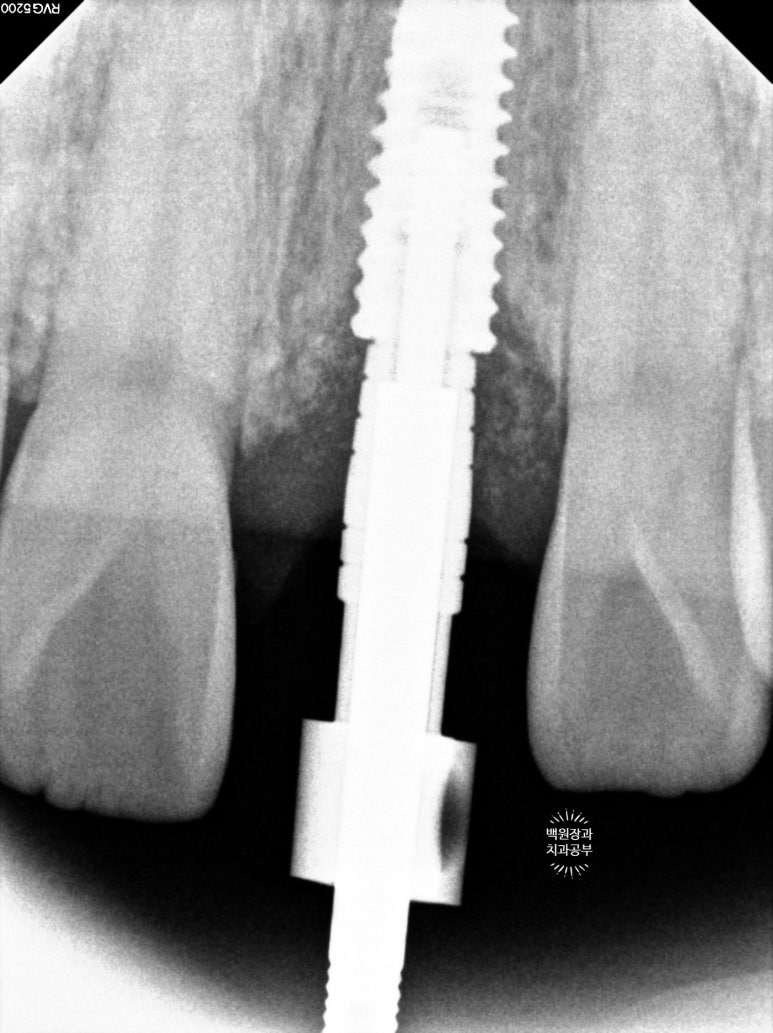

뽄뜨는 날 임플란트와 주변 뼈와의 관계를 평가하기 위해

작은 치근단 촬영도 함께 시행하는데요,

임플란트 주변의 뼈와 이식된 뼈이식재들이 잘 유지됨을 간접적으로 확인할 수 있었습니다.

사실 엑스레이로 찍어놓으면 엄청 임플란트 그 자체입니다.!!!

적절히 가운데에 심겨진 임플란트 덕분에 자연스러운 보철물을 만들 수 있었습니다.